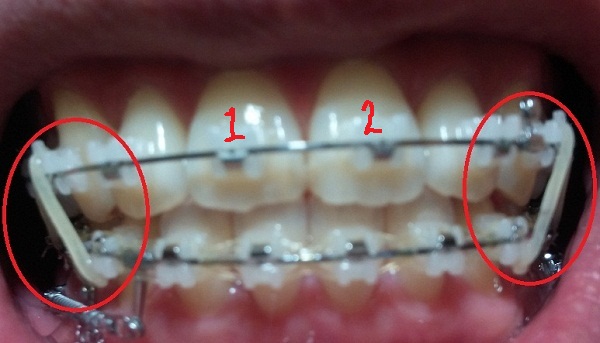

[고무줄 정면]

[고무줄 왼쪽]

[고무줄오른쪽]

-고무줄착용하기(전 치료와 동일)

-일회용 고무줄로 치아를 다물 때, 뜨는 공간이 없게

상악 송곳니와 하악 송곳니를 당기는 중!!